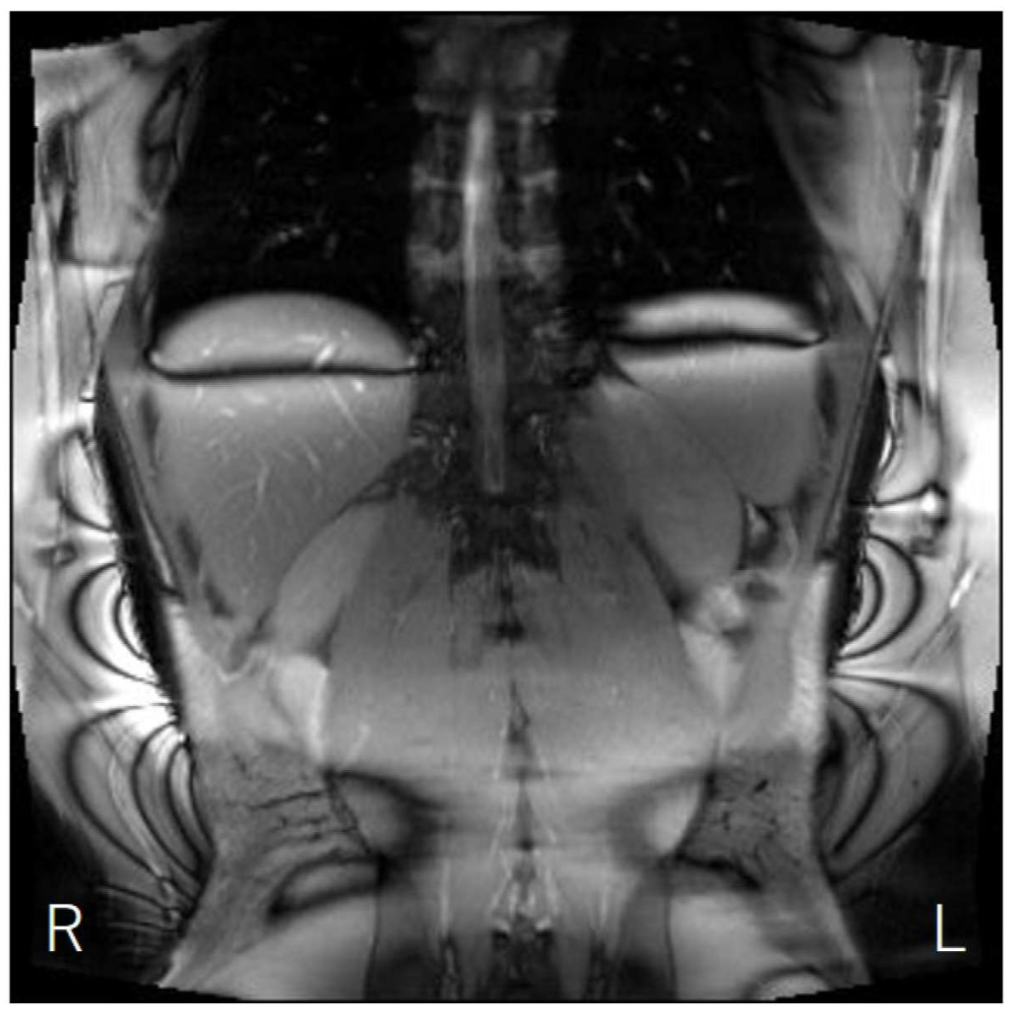

問題 17 腹部のSSFP像を示す。これらのアーチファクトを改善する方法はどれか。2つ選べ。

1. TRの延長

2. 局所シミング

3. マトリクス数の増加

4. オーバーサンプリング

5. キャリブレーションデータの再取得